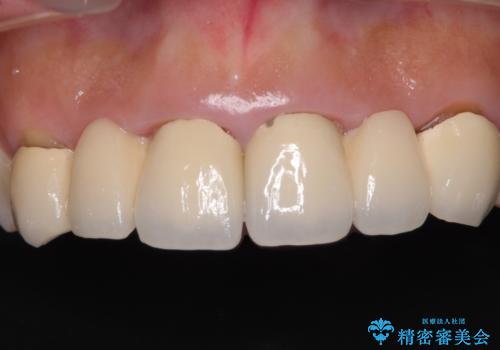

- 審美的ではない上の前歯とデコボコの下の前歯、歯茎が腫れている奥歯を気にして来院された患者様です。

根管治療の必要な歯がいくつかあるため、まずは根管治療を行い、その後インビザラインにて矯正治療を行うこととしました。

矯正治療後に前歯をセラミックブリッジに、奥の銀歯はセラミックインレーやPGAインレー(ゴールドインレー)にて補綴・修復治療を行うこととしました。

矯正治療により下顎前歯を整列させたため、上顎前歯のセラミックブリッジを補綴することで口元を少し下げることができました。